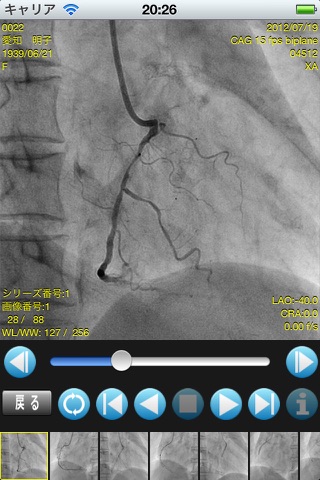

マルチフレームDICOM PACS日本国内トップシェアのGOODMANが、iPad専用のビューアーをリリースしました!

・MultiFrame DICOM画像をダウンロード、閲覧することが出来ます。

・画像再生機能(再生・停止、リピート、画像送り・戻し、コマ送り・戻し)

・横向きにした場合の2分割表示